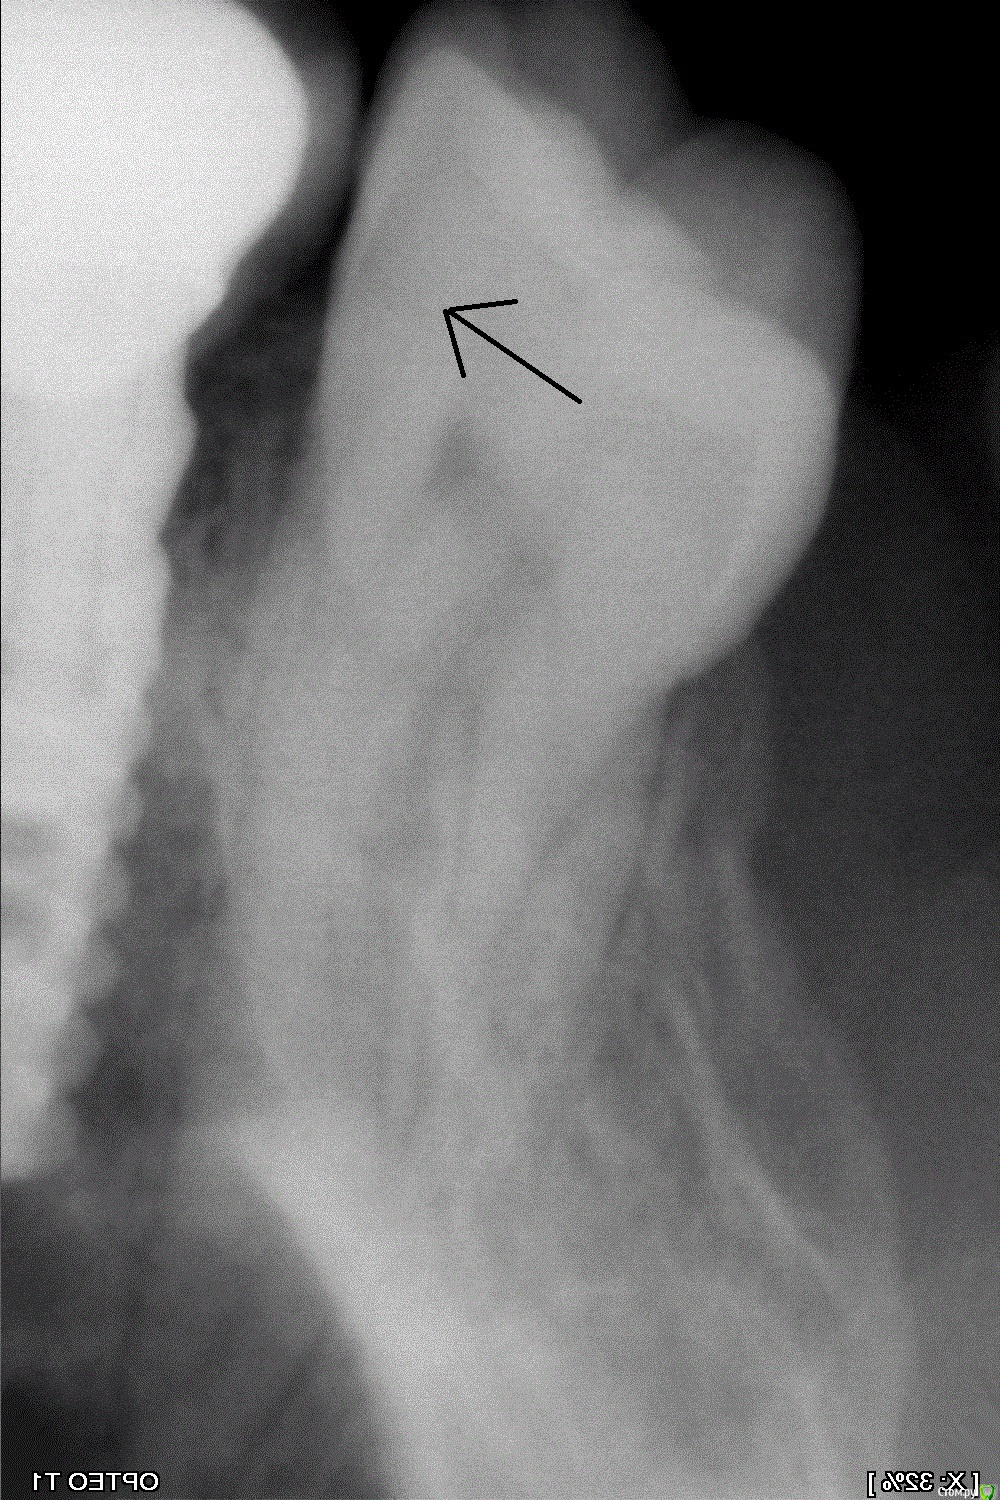

Shamxal Опубликовано 17 января, 2015 Поделиться Опубликовано 17 января, 2015 Всем здрасти. Не хочу открывать новую тему. Так же нужна помощь. Имланты стоят 2 года. Неделю назад зуб начал реагировать на холод. Объективно видимая часть зуба не повреждена. А вот на снимке есть сомнения насчет кариеса Ссылка на комментарий

CRAZYDUCK Опубликовано 17 января, 2015 Поделиться Опубликовано 17 января, 2015 Всем здрасти. Не хочу открывать новую тему. Так же нужна помощь. Имланты стоят 2 года. Неделю назад зуб начал реагировать на холод. Объективно видимая часть зуба не повреждена. А вот на снимке есть сомнения насчет кариесаЭмаль интактная , мне кажется нет там кариеса , может клиновидный дефект дает чувствительность? Ссылка на комментарий

St. Опубликовано 19 января, 2015 Поделиться Опубликовано 19 января, 2015 Всем здрасти. Не хочу открывать новую тему. Так же нужна помощь. Имланты стоят 2 года. Неделю назад зуб начал реагировать на холод. Объективно видимая часть зуба не повреждена. А вот на снимке есть сомнения насчет кариесаНету там кариеса, мне тоже так кажется. Что с десной? Рецессия есть? Как чувствительность остальных зубов, не повышена? Ссылка на комментарий

nelya Опубликовано 21 января, 2015 Поделиться Опубликовано 21 января, 2015 P. S. А так да, я тоже кариеса по снимку не вижу. Ссылка на комментарий